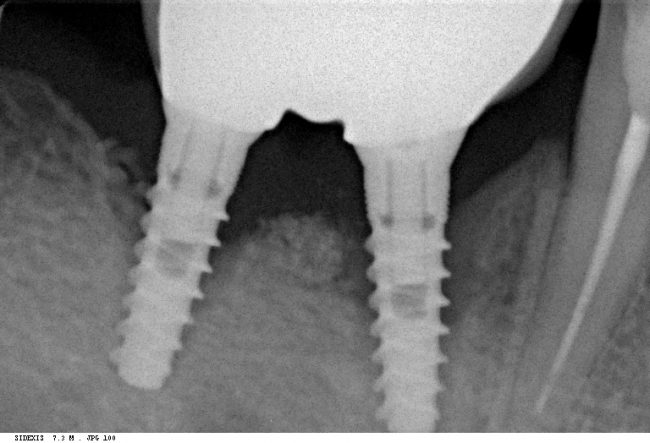

Мы сделали рентгеновские контрольные снимки —  панорамный для оценки положения имплантатов и прицельный для контроля посадки абатментов.

На последнем видно, что абатменты (особенно правого на фото зуба) не сели на свои места, между ними и платформами имплантатов есть щель — и эта ситуация наглядно демонстрирует, ПОЧЕМУ такие снимки необходимы. Мы вернули пациентку в хирургический кабинет и провели коррекцию абатмента (уменьшили ширину трансгингивальной части), После чего, проводили пациентку в кабинет стоматолога-ортопеда для временного протезирования.

После фиксации временных коронок мы делаем прицельный контрольный снимок для контроля посадки абатментов на платформу и оценки качества изготовления композитных реставраций.

Вот клиническая картина и рентгенологический контроль через 2,5 года после имплантации и протезирования:

Данные конусно-лучевой компьютерной томографии области имплантации через 2,5 года выглядят более интересными:

Как видите, под приемлемыми объёмами и состоянием десны в области имплантатов скрывается надёжный фундамент — восстановленная и сохраненная с помощью аугментации костная ткань, состояние которой за два с половиной года только улучшилось.